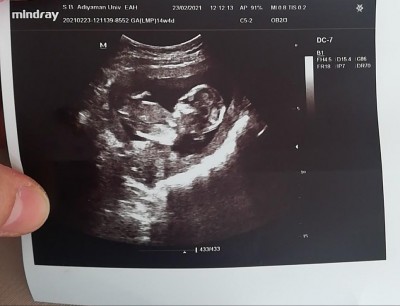

Tahminlerinizi bekliyoruz hamişler 12 hafta